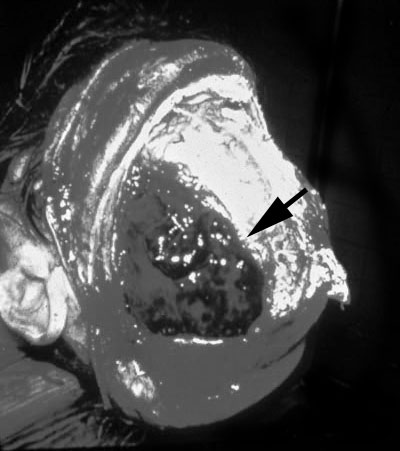

Traumatic epidural hemorrhage, gross

Traumatic epidural hemorrhage (arrow), seen upon opening the skull, prior to reflection of the dura.